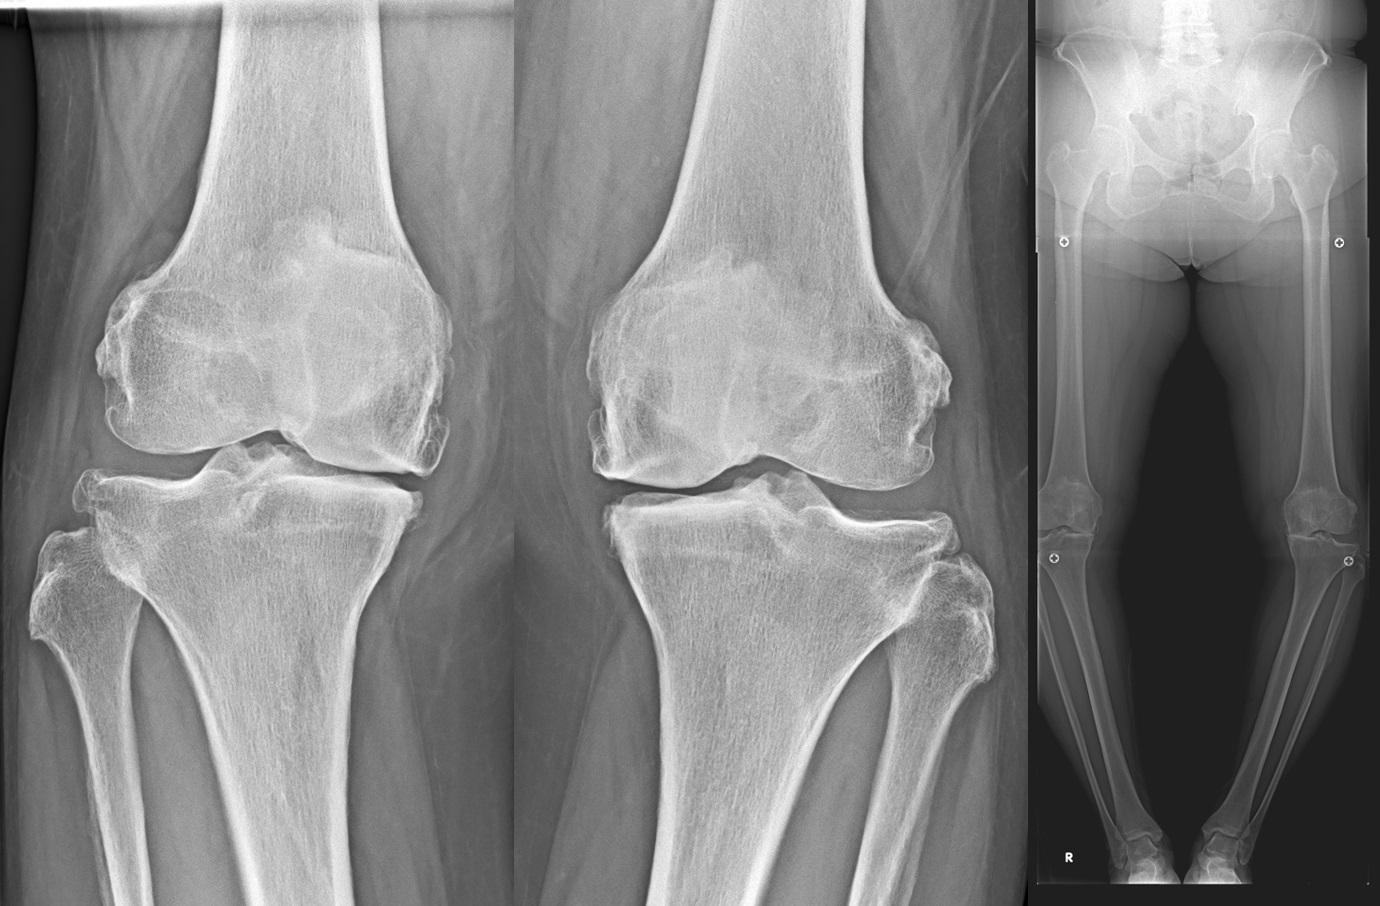

変形性膝関節症(knee osteoarthritis: 膝OA)

変形性膝関節症は、加齢などにより関節軟骨や半月板が変性・消失する疾患で膝関節痛や可動域制限を生じ、病態が進行すると日常生活動作(ADL)や生活の質(QOL)が低下します。わが国では40歳以上の有病者数は2500万人と推定されており、今後の高齢者人口の増加に伴い有病者数も増加すると考えられています。

人工膝関節単顆置換術(unicompartmental knee arthroplasty: UKA)

膝関節の内側または外側のみの変形に対して適応があります。

人工膝関節全置換術(total knee arthroplasty: TKA)

末期の変形性膝関節症に対してはTKAを行います。